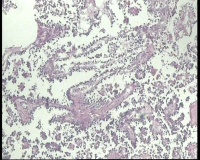

| 性别 | 女 | 年龄 | 53岁 | 临床诊断 | 右侧卵巢囊肿 |

| 一般病史 | 彩超:盆腔可见囊实性回声,囊性为主,大小约5.0x3.7厘米,其内可见分隔回声,部分分隔内回声不纯净,形态欠规整 | ||||

| 标本名称 | 腔镜下右侧卵巢囊肿手术 | ||||

| 大体所见 | 囊壁样组织5.5x5.0厘米,4.5x2.5厘米2块,壁厚0.1-0.2lm,囊壁大部分光滑,局灶见0.7x0.5x0.3厘米淡黄色突起组织,另见淡黄色、肉粉色质软组织2.8厘米一堆。 | ||||